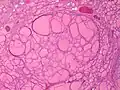

Diffuse thyroid hyperplasia typically shows variably sized follicles Thyroid hyperplasia with a hyperplastic nodule. It characteristically has no capsule (distinguishing it from thyroid adenoma or carcinoma).

Thyroid hyperplasia with a hyperplastic nodule. It characteristically has no capsule (distinguishing it from thyroid adenoma or carcinoma)..jpg.webp) The follicular linings may be thickened, with papillary projections (but lack nuclear features of papillary thyroid carcinoma)

The epithelium may also be flattened by enlarged follicles. It can show hypercellular or microfollicular areas. There is no surrounding capsule (in contrast, a thyroid follicular adenoma or carcinoma is generally encapsulated).